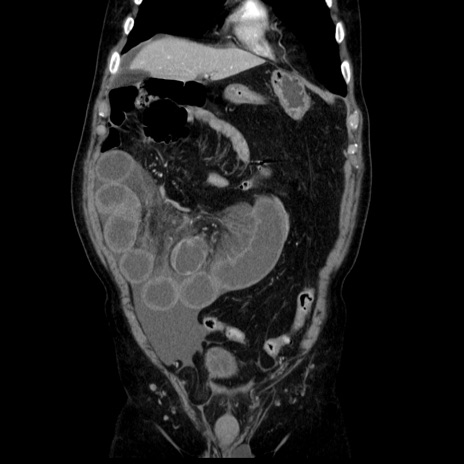

症例30(冠状断像)

【症例】80歳代男性

【主訴】臍周囲痛

【現病歴】約6時間前から臍下部痛が出現。次第に腹部膨隆・背部痛も生じてきたため来院。背部痛の場所は変化しない。

【身体所見】意識清明、BT 36.3℃、BP  131/87mmHg、P 87bpm、SpO2 100%(RA)、臍周囲自発痛・圧痛あり、反跳痛なし、自発痛部位に一致して板状硬あり、腹部膨隆、腸雑音減弱、CVA tenderness両側陰性。

【データ】WBC 19600、CRP 0.33